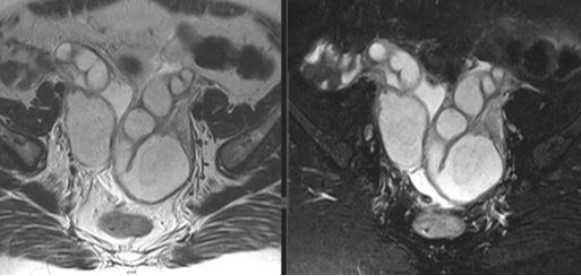

МРТ малого таза в корональной плоскости. В структуре левого яичника отмечаются:

— с толстыми и неровными стенками киста желтого тела (круг),

— функциональная геморрагическая киста (регрессирующее желтое тело).